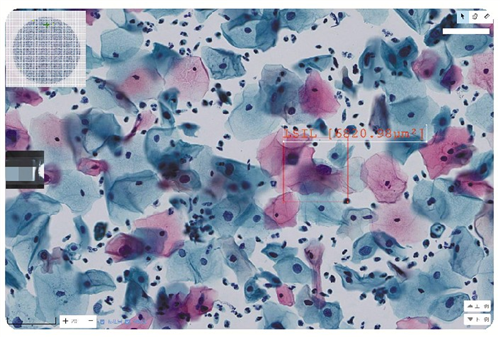

病理切片扫描图像

病理诊断需要对复杂多样的关键组织结构进行精准定性及定量分析,数据量惊人。以癌症组织来说,单个切片虽然只有指甲盖大小,但多切片的扫描图像,高达数十亿像素。数十亿像素背后,蕴藏着无数的身体密码和疾病信息。医生要长时间、高强度观看显影后的胶片,工作容易造成视觉疲劳,可能影响判断的准确性。

通过不断的积累临床案例,以及算法模型的不断演进,AI逐渐成长为病理医生的助手。目前,AI已在宫颈液基细胞学应用上“学有所成”。

在病理科细胞学组,医生刘俊许、杜丹凤、张士岭在对AI筛选出的“阳性”病例进行复核。“每个切片里可能有两三万个细胞,要用肉眼逐一检查,耗费的时间和精力相当庞大。”关于AI在细胞学诊断的准确性,病理医生的反馈是“AI是一位非常严苛的助手,它判定‘阳性’的标准相对较低,宫颈细胞核形态或者浆比稍有异常,就会定为‘阳性’,并将可疑的病变细胞圈注出来提醒医生关注”。